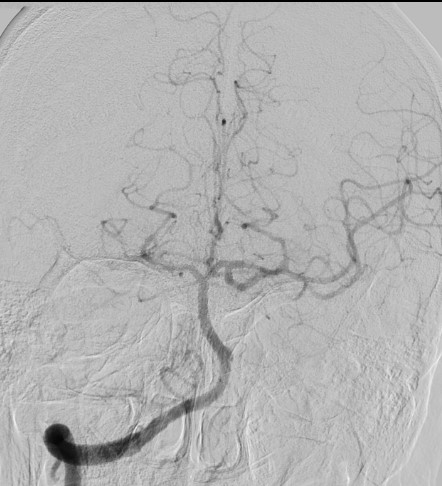

13:00 Больной подан в рентгеноперационную, выполнена церебральная ангиография: Ангиографические признаки атеросклеротического процесса брахиоцефальных артерий, тромботической окклюзии правой ВСА(Рис1), окклюзия левых ВСА(Рис3) и ПА(Рис2).

рис. 1 рис. 2